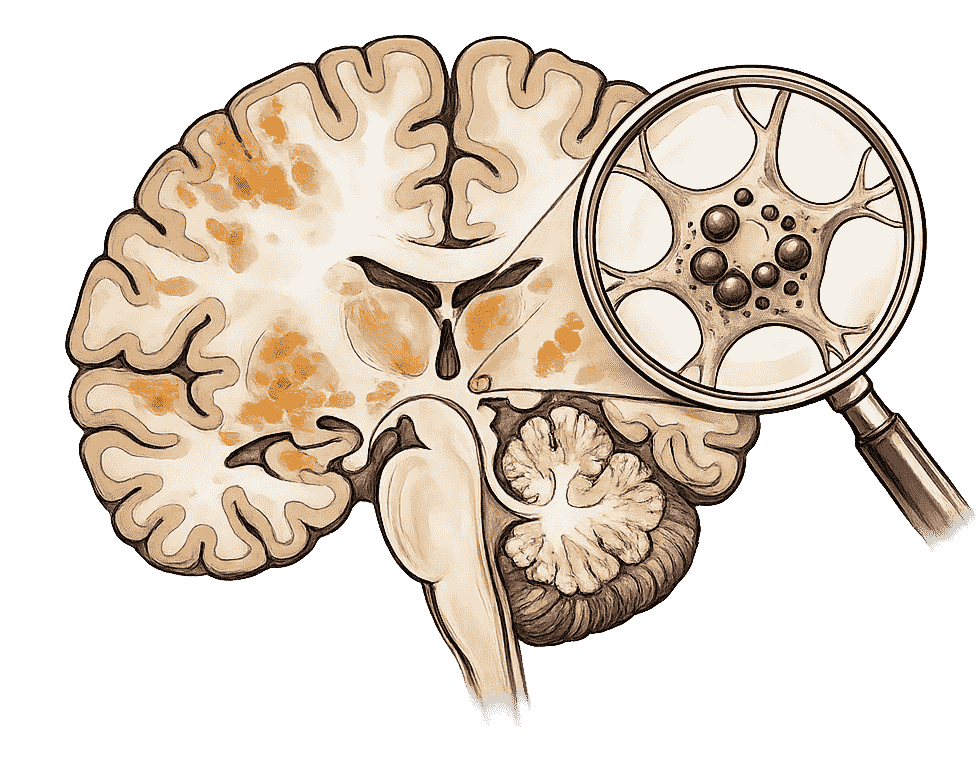

In Ayurveda, brain atrophy is understood as a condition involving Vata dosha aggravation along with depletion of Ojas, the vital essence responsible for mental resilience, immunity, and neurological strength. The deterioration of higher mental faculties Dhi (intellect), Dhriti (retention), and Smriti (memory) is central to this condition. Weak Agni (digestive fire), chronic inflammation, oxidative stress, ageing, and impaired circulation lead to accumulation of Ama (metabolic toxins), obstructing subtle channels (Nadis) that nourish the brain and spinal system. Ayurvedic care focuses on pacifying Vata, enhancing Ojas, nourishing nerve tissues, and supporting long-term cognitive stability.